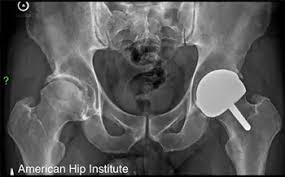

Osteoporosis is a bone-weakening condition that can sneak up on you like an unexpected twist in a mystery novel. The disease causes a gradual weakening of bone density and quality, making them more vulnerable. Over time, this imbalance can lead to porous, brittle bones, increasing the risk of fractures, especially in the hip, spine and wrist. Osteoporosis often progresses without symptoms until a rupture occurs, earning it the nickname “the silent disease.” Talk to your healthcare provider about when to get a bone density test, especially if you’re at risk.